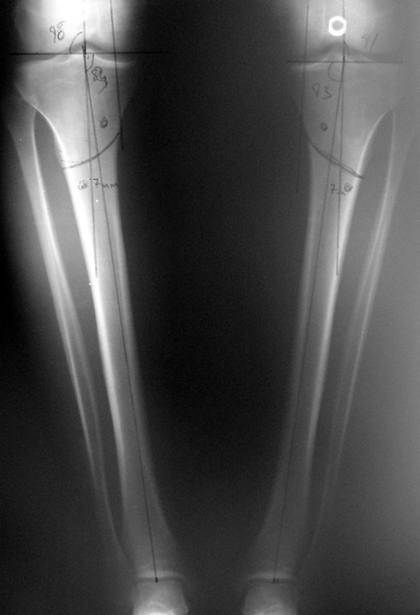

İntramedüller çivinin yerleştirilmesi ve osteotomi: Hasta traksiyon masasına supin pozisyonda yatırılır ve sağlam bacak altta olacak şekilde bacaklar makas pozisyonuna alınır. Standart yolla piriformis çukurundan medulla içine girilir ve kılavuz tel üzerinden kullanılacak çividen 1.5 mm daha kalın oyucu ile medulla oyulur. Proksimal femur, çivinin proksimali daha kalın olduğu için daha kalın oyulur. Radyografide osteotomi hattı planlaması yapılır. Planlama yapılırken uzatma sonunda distalde en az 8 cm. çivi kalması stabilizasyon için gereklidir. Kortikotomi perkütan olarak kortikotom ile tamamlanır. Daha sonra kılavuz tel çivinin boyunu ölçmek için distale ilerletilir. Uygun boyda intramedüller çivi çakılır. Son olarak çivi proksimalden kilitlenir ve bir adet dren konarak ameliyatın birinci kısmı tamamlanır.

Eksternal fiksatör uygulanımı: İntramedüller çiviye değmeden aşağıya ve yukarıya üçer adet Schanz vidası gönderilir. Vidalarla çivi arasında en az 1 mm den fazla mesafe olmalıdır.

Biz son zamanlarda, seçilmiş vakalarda, uzatma sonrası uzunluğu ve “alignment’ı” korumak amacı ile unilateral dinamik aksiyel fiksatör ve kilitli intramedüller çivi kombinasyonunu tercih etmekteyiz. Bu yöntemin ön şartları medullanın en dar çapının 7 mm.’den geniş olması ve uzatma sonrası distalde en az 8 cm. uzunluğunda çivi kalabilmesidir. İntramedüller çivi hem uzatma esnasında femurun üzerine gelen makaslama ve bükülme kuvvetlerini nötralize etmekte hem eksternal fiksasyon süresini kısaltmakta, hem de yeni oluşan kemiği kırıklara karşı korumaktadır. Serimizde bir vakada subtrokanterik femoral osteotomi yapılmıştır. İntramedüller çiviye rağmen varus angulasyonu oluşması yönünde bir dezavantaj tespit etmedik.